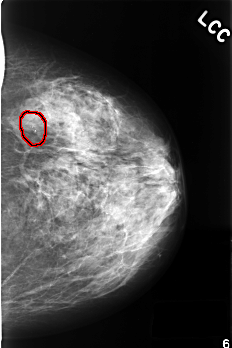

C_0379_1.LEFT_CC

FILE: C_0379_1.LEFT_CC.OVERLAY

TOTAL_ABNORMALITIES 1

ABNORMALITY 1

LESION_TYPE CALCIFICATION TYPE PLEOMORPHIC DISTRIBUTION CLUSTERED

ASSESSMENT 4

SUBTLETY 5

PATHOLOGY BENIGN

TOTAL_OUTLINES 1

BOUNDARY

LEFT_CC LINES 4520 PIXELS_PER_LINE 3008 BITS_PER_PIXEL 12 RESOLUTION 50 OVERLAY